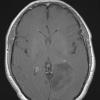

NEOPLASMS (GLIAL)

Astrocytoma, IDH-mutant, WHO Grade 2 (2)